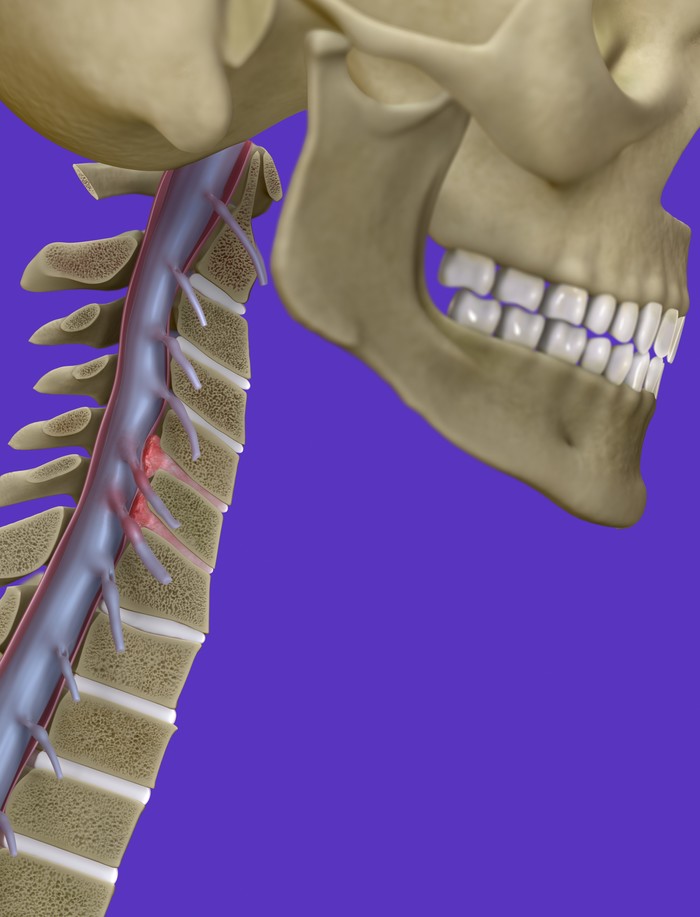

목 디스크는 목의 디스크(경추 디스크)에서 출현하는 질환으로, 경추 디스크 사이의 연골판이 터져 디스크 내부 물질이 경추 신경을 자극해 통증이나 저림증 등의 증상을 유발 해요. 목 디스크는 일상생활에서의 안 좋은 자세나 많은 운동, 부상 등이 이유가 되는 것이 될 수 있기도하고, 시간이 지날수록 발생 확률이 높아져요. 목 디스크의 증상으로는 목 부위의 통증, 팔의 저림, 근육 약화 등이 있으며, 증상이 난폭한 경우 수술 등의 치료가 필요할 수 있어요. 그리하나 대개의 경우 치료 없이도 시간이 지나면 증상이 호전되는 경우가 대부분입니다.

목디스크 증상은 엄지손가락과 새끼손가락이 저리고 아픈 것이 인상적인데 이러한 증상이 나타나게 되면 손에 힘을 주기가 힘들고 육체활동실력이 저하되며 우리 몸의 근력이 약해지게 되기도 합니다. 목에서 걸치는 신경이 어깨나 손가락까지 연결되게 되어지고 있는데 이 신경이 눌리게 되면 어깨는 물론이고 손가락이 저리게 되면서 힘을 죽 뭔가를 하시는게 어려운 상태가 된다고 합니다.

목디스크가 생겨나게 보면 어깨에서부터 팔을 지나 엄지손가락까지 저리고 아프게 되면서 7번과 8번 신경이 눌려지게 되어 손과 손가락 마디마디가 저리고 통증이 있고요. 이 통증이 팔, 어깨에서 손 및 손가락 등으로 방사하게 되고 있는데 이때 신경 분포에 따라서 대부분 5번 신경이 눌리게 되면서 어깨가 아프고, 6번 신경까지 눌리게 되면서 통증은 더 심해진다고 하더라고요.

추간판의 수핵이 빠지거나 퇴행성 경추증 및 경추관협착증 등으로 척수가 압박되면 대다수 팔에 힘이 빠지는 것을 느끼게 돼요. 척수가 눌리는 정도이기 때문에 한쪽 팔만 마비될 수 있고요. 하지마는 양팔의 감각이 둔해지고 눈을 감고도 어지럽기 때문에 이러한 목 디스크 증상이 나타나면 무척 위험한 상태가 되기 때문에 빨리 치료가 필요해요.

척수라는 중추 신경은 목뼈를 통과해 목 아래 감각과 운동 신경에 영향을 끼치기 때문에 목 디스크 증상들이 나타나면 신속하고 빠른 대처가 필요해요. 목디스크 치료형식으로 주로 초기 스탭에는 물리치료나 약물을 통해 대개의 환자들이 호전돼요. 그렇지 않다고 하면 신경 성형술과 차단술이라고 부르는 뼈주사 목디스크 치료방법을 이용하는데, 이 치료방법은 통증이 있는 신경 부위에 약물을 삽입하는 것입니다.